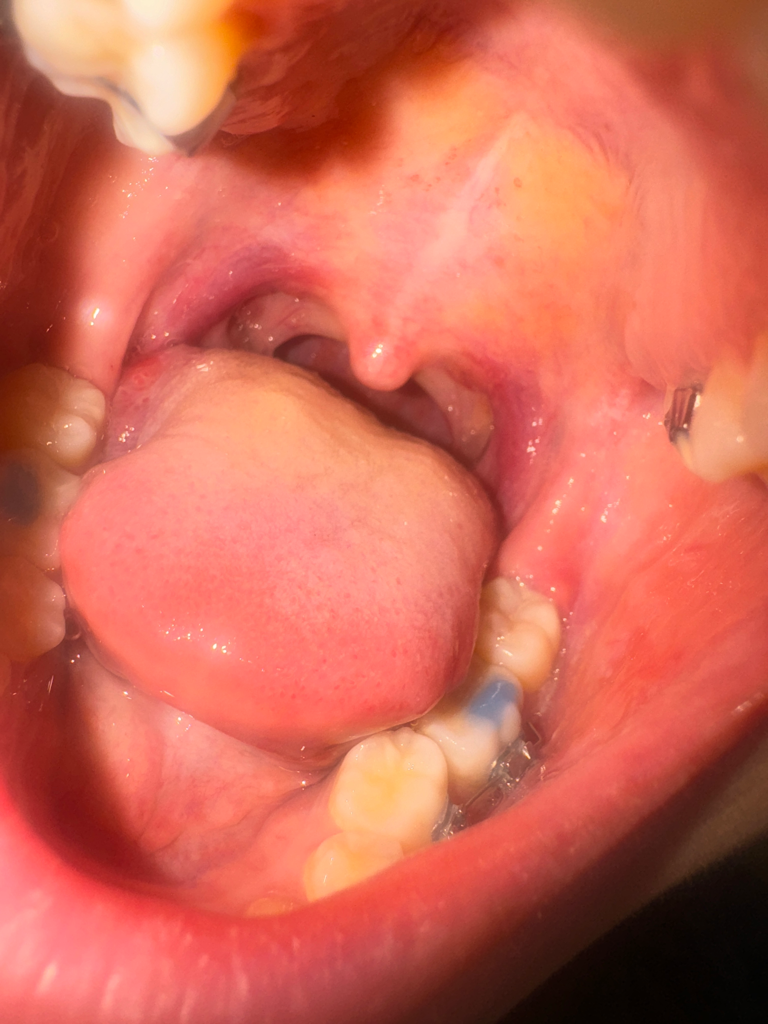

사진으로 봤을 이때는 드라이 소켓이 보이거나 하지는 않습니다. 바 사랑니를 발치하고 나면 발치 한 부위가 자극되지 않도록 하는 것이 좋습니다. 사랑니를 발치한 부위가 자극이 되어 손상이 생기게 된다면 치유가 늦어질 수 있기 때문입니다.

드라이 소켓은 감염의 일종으로 통증이 심하고 냄새가 날수 잇습니다. 드라이 소켓은 아닌거 같고, 잇몸이 치유되면서 자연스러운 현상입니다.

하얀 상피세포가 차오르면서 낫습니다. 드라이소켓이 생기면 엄청난 통증이 있으니 걱정안하셔도 됩니다.

혈병이 형성된 것으로 보이며, 아물어가는 과정이기에 걱정하지 않아도 됩니다. 통증이 있는 경우 소염진통제 복용이 증상경감에 도움이 됩니다.

일단, 발치 후 주의사항은 잘 지키셨고 소독도 잘 챙겨서 하셨으니 발치로 인한 부작용은 크게 없을 것으로 여겨집니다.

사진상으로도 크게 병적인 소견은 보이지 않습니다